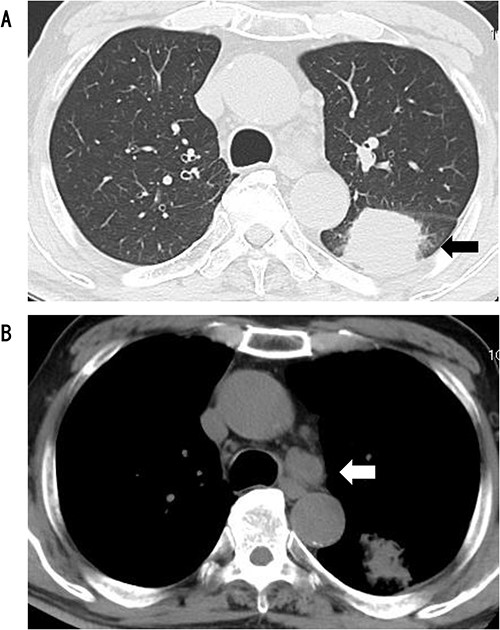

A 75-year-old male was referred to our hospital for preoperative examination of an abnormal chest shadow during orthopaedic surgery. Chest computed tomography (CT) revealed a mass nodule measuring 4.1 cm in S6 of the left lung, and the tracheobronchial lymph node (No 4 L) was enlarged (Fig. 1). Fluorodeoxyglucose positron emission tomography (PET) revealed abnormal accumulation with a maximum standardized uptake value of 20.4 at the mass, 9.4 at the lymph node and no metastases to other organs (Fig. 2). Based on the above findings, we diagnosed the patient with left lower lobe lung cancer (cT1bN2M0, c-Stage IIIA). The patient had no history of cardiovascular disease and was unaware of chest pain, such as an angina attack. We performed robot-assisted left lower lobectomy.

CT showed a circular mass measuring 4.1 cm in the S6 of the left lower lobe (A) and enlarged lymph node #4 (B).